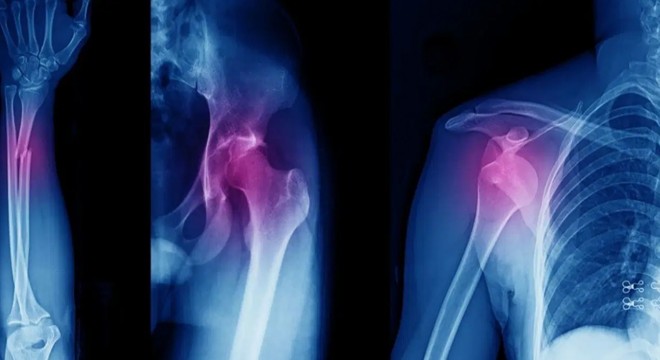

Kırık kemiklerin tedavisinde devrim niteliğinde bir yöntem geliştirildi. Güney Kore’deki Sungkyunkwan Üniversitesi’nden bilim insanları, modifiye edilmiş bir tutkal tabancasıyla ameliyat sırasında 3D baskı yöntemiyle kemik grefti üretmeyi başardı. Bu yöntem, hem operasyon süresini kısaltıyor hem de antibiyotik salınımıyla enfeksiyon riskini azaltarak hastaların iyileşme sürecini hızlandırıyor.